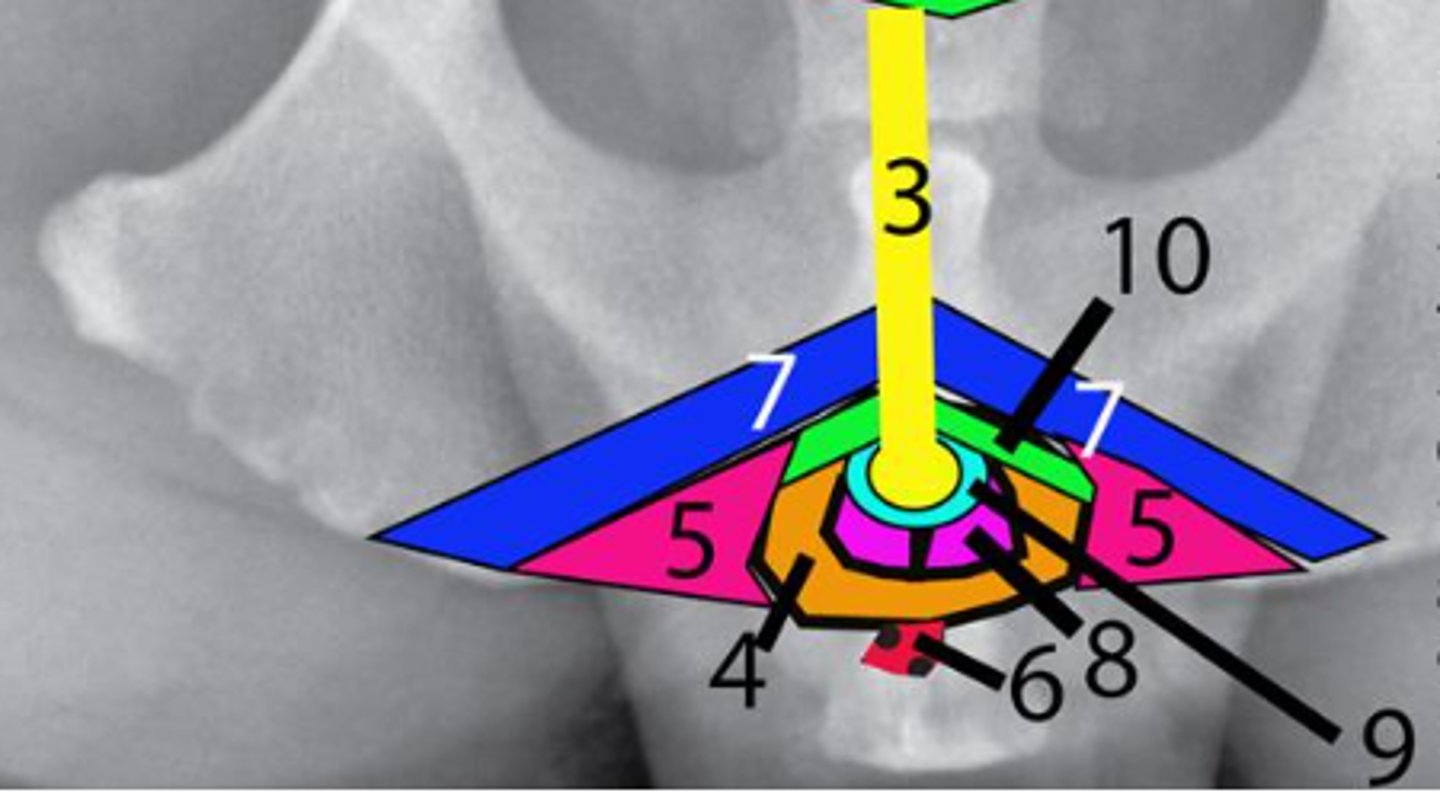

Bladder

Identify #1

Prostate

Identify #2

Urethra

Identify #3

Bulbospongiosus muscle

Identify #4

Ischiocavernosus muscle

Identify #5

Retractor penis muscle

Identify #6

Ischiourethralis muscle

Identify #7

Bulb of the penis

Identify #8

Corpus spongiosum

Identify #9

Corpus cavernosum

Identify #10